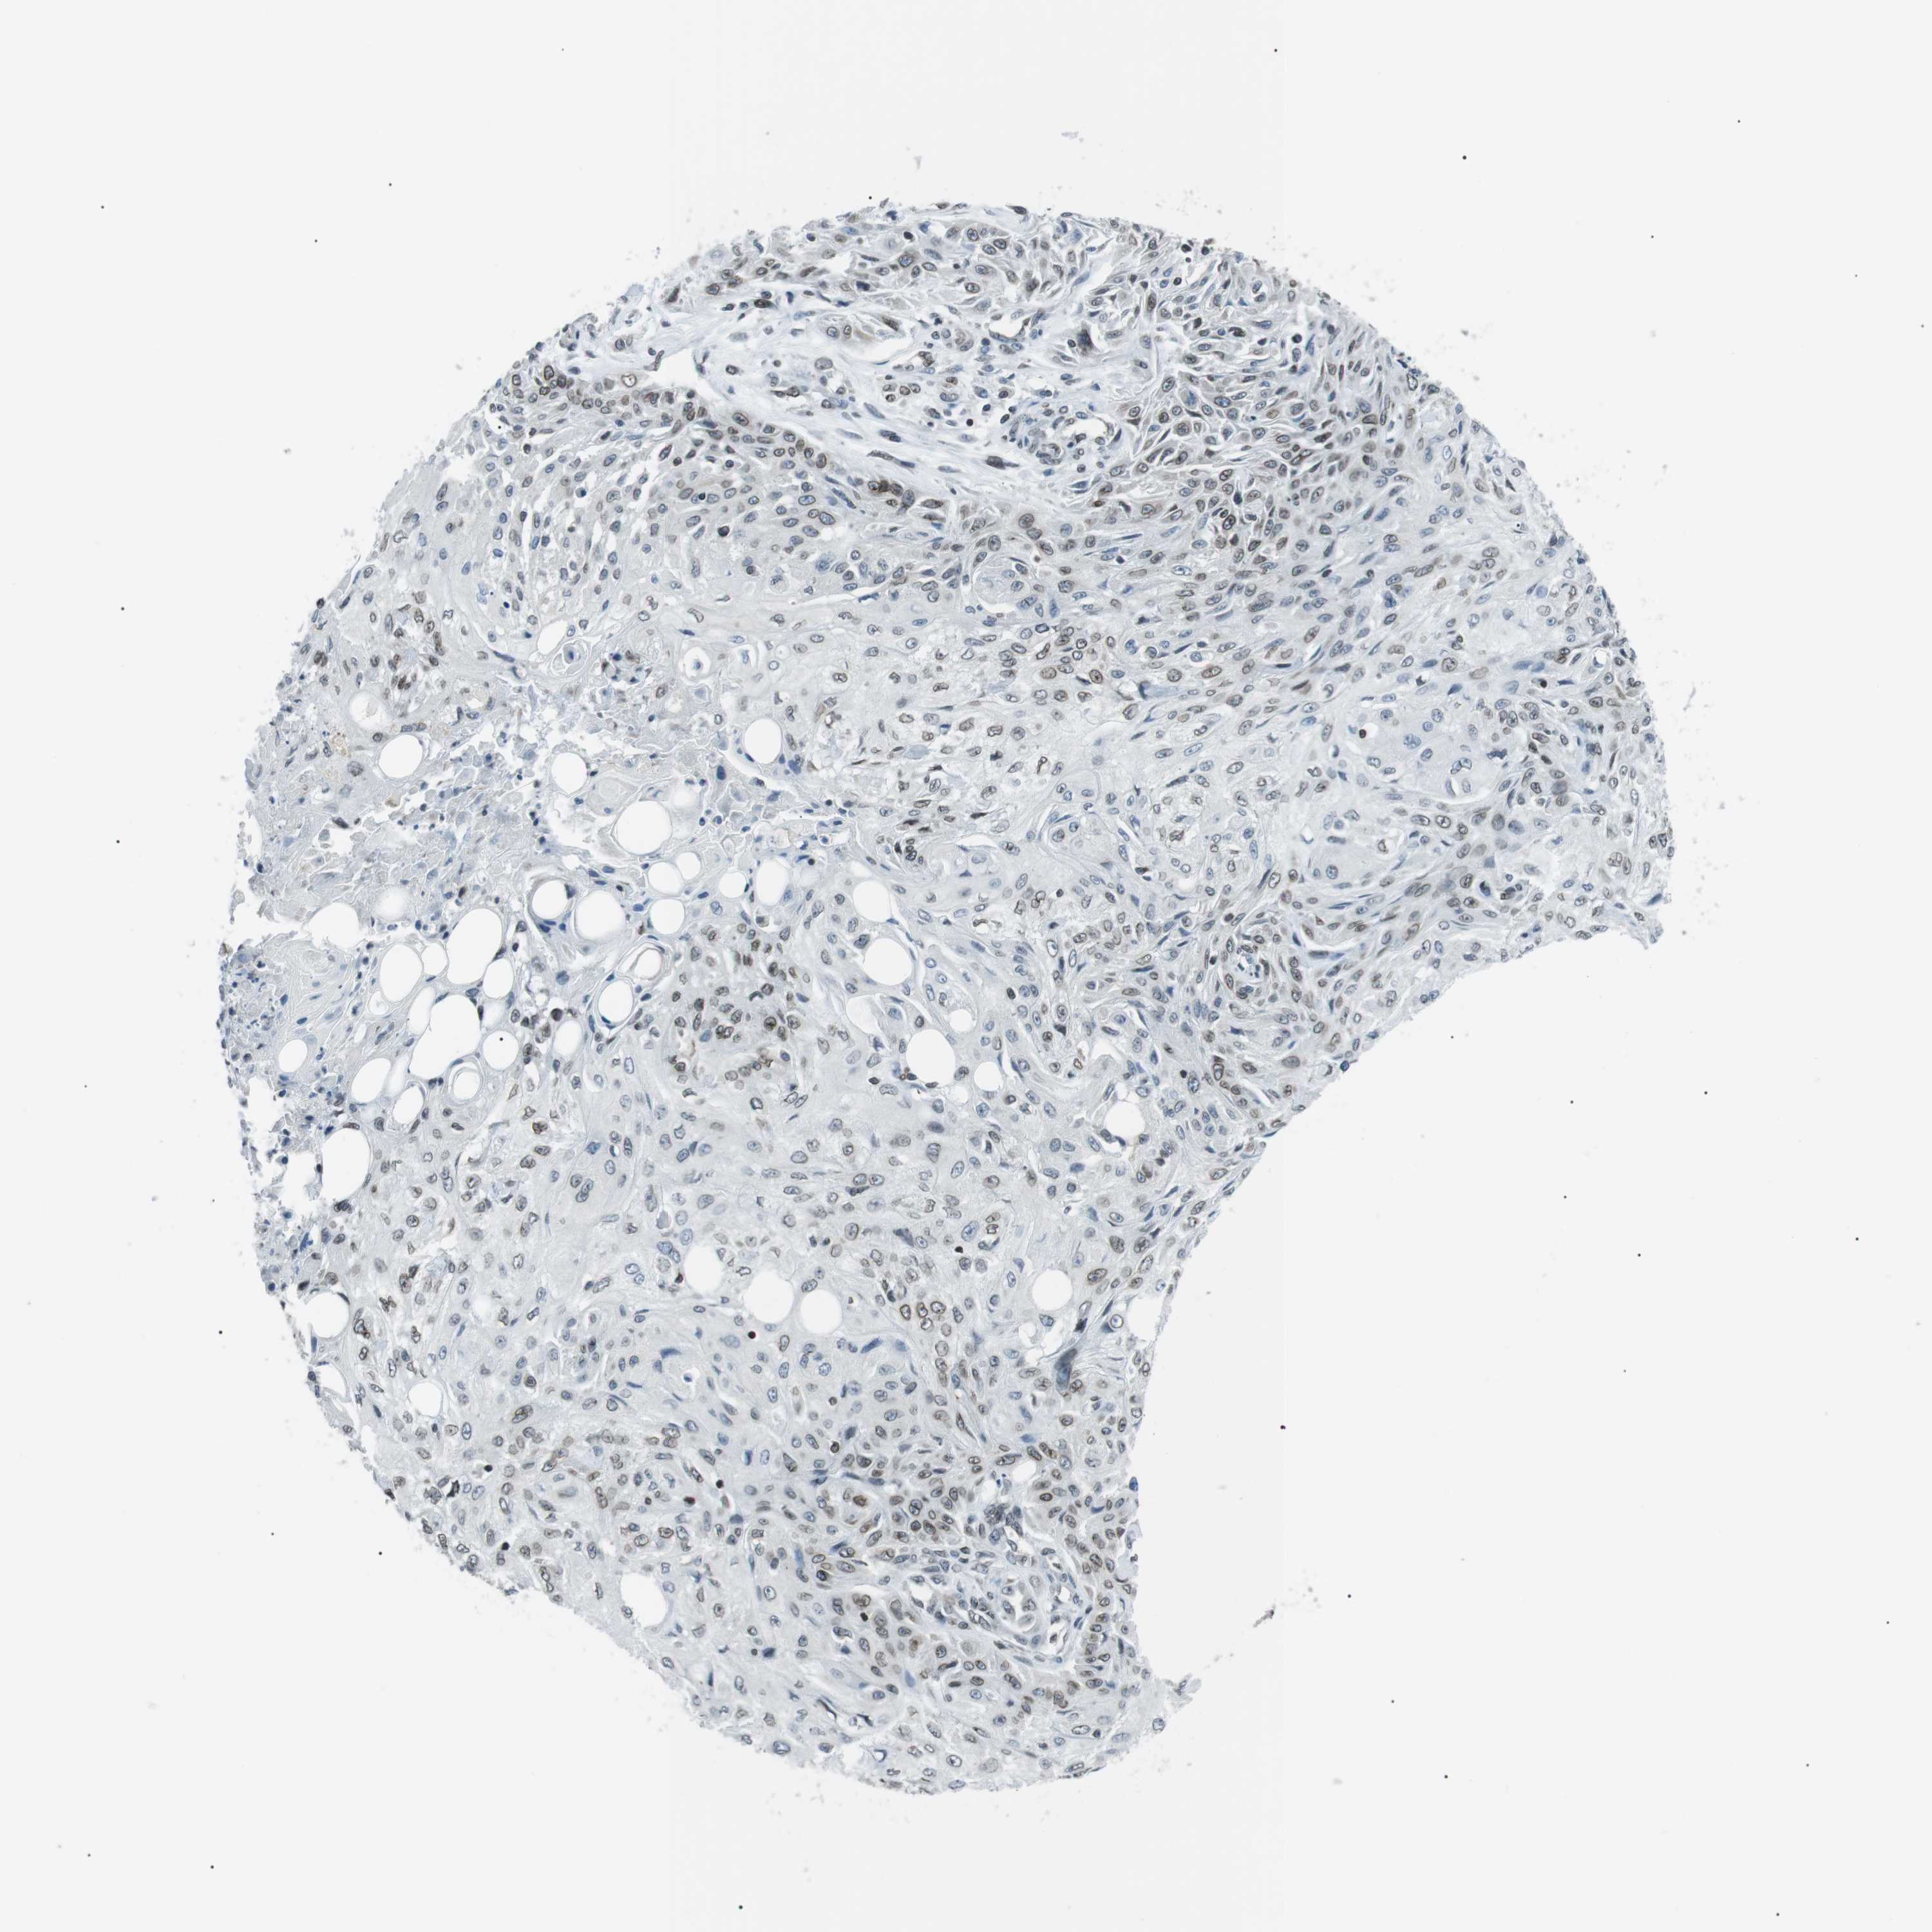

Basal cell and squamous cell cancer

SKIN CANCER - Protein expressioni

A mouse-over function shows sample information and annotation data. Click on an image to view it in a full screen mode. Samples can be filtered based on level of antibody staining by selecting one or several of the following categories: high, medium, low and not detected. The assay and annotation is described here.

Antibody stainingi

Antibody staining in the annotated cell types in the current human tissue is reported as not detected, low, medium, or high, based on conventional immunohistochemistry profiling in selected tissues. This score is based on the combination of the staining intensity and fraction of stained cells.

Each image is clickable and will lead to virtual microscopy that enables deeper exploration of all samples and also displays staining intensity scores, fraction scores and subcellular localization as well as patient and tissue information for each sample.

Antibody HPA000399

Antibody HPA015752

Staining

High

Medium

Low

Not detected

Intensity

Strong

Moderate

Weak

Negative

Quantity

>75%

75%-25%

<25%

None

Location

Nuclear

Cytoplasmic/membranous

Cytoplasmic/membranous,nuclear

Squamous cell carcinoma, NOS

Squamous cell carcinoma, metastatic, NOS

Basal cell carcinoma

Squamous cell carcinoma in situ, NOS

Adnexal tumor, benign